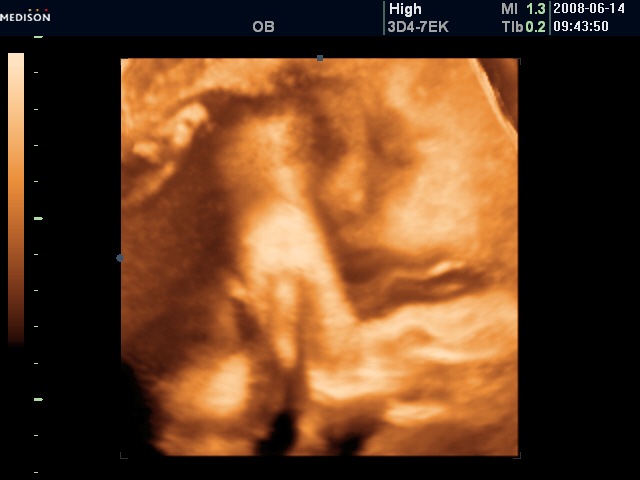

No for the fun, the sonogram. Yang wanted to double check that it was indeed a girl and indeed that has been confirmed. The doctor checked the baby’s development and it is right on tract. Almost right in the middle of normal. They then took some pictures. Here’s the future Beijing allio girl:

The feedback is the nose is bigger than they typical Chinese but I suspect not bigger than the typical allio.